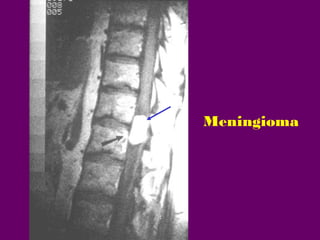

U MAØNG NAÕO

(MENINGIOMA)

a.Tæ leä : 25-45%.

b.Tuoåi vaø giôùi : 50-60 tuoåi.

80% ôû nöõ.

c.Vò trí :

-65-80% ôû ngöïc, phaàn coøn

laïi ôû coå.

-85% ngoaøi tuyû-trong maøng

cöùng, 15% ngoaøi maøng

cöùng.

d.MRI :

MENINGIOMA

X quang qui öôùc

Cheøn eùp tuûy ngang

D8

Khoa Chaån ñoaùn hình aûnh /Bv Chôï

Bn.Nguyeãn Thò H.C. 1934 SHS: 7089

Hình T1W

Hình T2W

Hình T1W+Gd